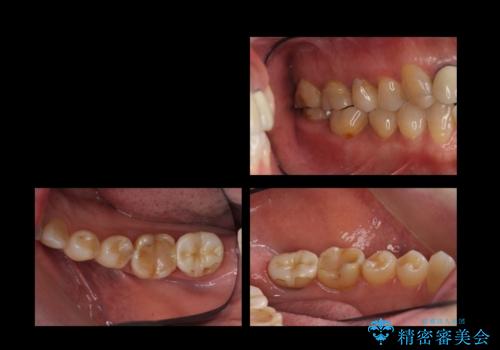

- 右下奥歯(7番)の高さがなく、かぶせ物(クラウン)にするためにあらかじめ歯周外科手術を行いました。(クラウンレングスニング)

右下5番は歯ぐき付近までWSD(くさび状欠損)で削れていたため、患者様と相談してクラウンにしました。その際、削れていたのが歯肉縁下に及んでいたため、一緒に手術範囲に含めました。

歯の高さを出すとかぶせ物(クラウン)がはずれにくくなります。

今回は右下7番が神経のない歯だったため、クラウンにして割れにくくしています。